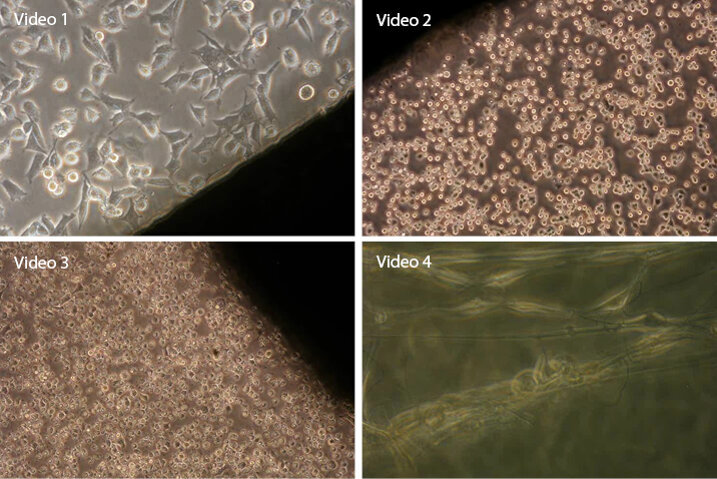

Tyto statické metody mají svůj nezastupitelný význam při studiu toxicity materiálů a jednoznačně určují, kdy může být materiál pro aplikaci užit a kdy ne. Vedle těchto metod existují, třebaže poněkud opomíjené, metody řekněme dynamické. Ty jsou založeny na průběžném snímkování rostoucí buněčné populace, samozřejmě in vitro. Princip sběrného snímkování je znám od doby samotného vynálezu fotografie a zajímavé je, že první využití bylo v biologii. Moderně se metodě říká „live cell dynamic image“, český termín je již 100 let znám jako „sběrná kinematografie“, což ovšem nemá nic společného s dramatickými pořady některých tvůrců filmových dokumentů. V našem případě jde o sběrnou mikrokinematografii, to znamená postupné snímkování zorného pole mikroskopu, kde se odehrávají fyziologické buněčné jevy. Snímkujeme tedy chování buněčné populace v materiálem pozměněných kultivačních podmínkách. Znamená to, že na výsledném snímku vidíme vzájemné buněčné interakce, interakce buněk s materiálem a hlavně adaptační fázi populace na materiál nebo jeho výluh. Popřípadě také fakt, že zlomky materiálu indukují projevy taxe buněk směrem k úlomku nebo od něj.

Video 1: Zirkon – Pozitivní reakce na vzorek zirkonia. Buňky reagují dobrou adhezí a dilatací, probíhá buněčné dělení Video 2: Alzona – Kolem vzorku aluminia se postupně vytváří zóna odumírajících buněk, dál od povrchu vzorku jsou buňky živé Video 3: Indium – Zcela negativní reakce na vzorek india. Buňky reagují odumíráním, a to postupně od hrany vzorku. Video 4: Nanovlákno – Interakce buněk s mikro- a nanovlákny s PCL. Buňky adherují k vláknu, jsou schopny pohybu a co je důležité – dělí se. Reakce buněk je pozitivní.

Video 1: Zirkon – Pozitivní reakce na vzorek zirkonia. Buňky reagují dobrou adhezí a dilatací, probíhá buněčné dělení

Video 2: Alzona – Kolem vzorku aluminia se postupně vytváří zóna odumírajících buněk, dál od povrchu vzorku jsou buňky živé

Video 3: Indium – Zcela negativní reakce na vzorek india. Buňky reagují odumíráním, a to postupně od hrany vzorku.

Video 4: Nanovlákno – Interakce buněk s mikro- a nanovlákny s PCL. Buňky adherují k vláknu, jsou schopny pohybu a co je důležité – dělí se. Reakce buněk je pozitivní.